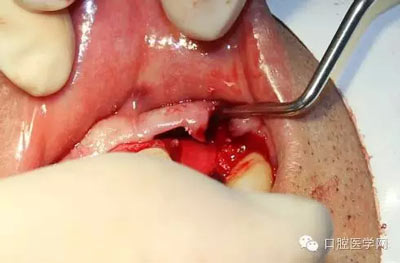

麻醉,切開,翻瓣

拔除松動22

翻瓣后可見11遠(yuǎn)中二壁深袋,骨質(zhì)缺損明顯。